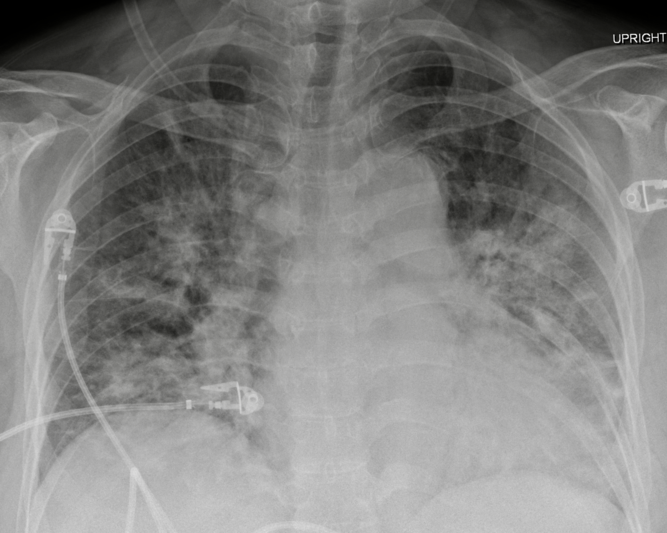

A 31-year-old male presented with a 2-year history of progressive headaches, nausea, vertigo, bilateral arm paresthesias, and blurry vision. His past medical history was unremarkable. A magnetic resonance imaging demonstrated an enhancing lesion of the posterior fossa and obstructive hydrocephalus. He underwent urgent suboccipital craniectomy and the surgical pathology was consistent with a WHO grade 4 medulloblastoma. After in-patient rehabilitation, the patient was discharged home on dexamethasone 4 mg twice daily (BID) with a plan for radiation followed by chemotherapy. Three weeks later, the dexamethasone dose was increased by the patient’s family physician to 8 mg BID. Three months after surgery, he presented acutely to the ED with a history of fever, chills, and dry cough. He had features of sepsis with tachypnea, tachycardia, and relative hypotension. His initial CXR was largely unremarkable and his oxygen saturation was normal on room air. He was started on broad spectrum antibiotics. Two days following his admission to the internal medicine team, he developed acute respiratory failure. Repeat CXR was most consistent with acute respiratory distress syndrome ( Figure 2). He was transferred to the ICU for intubation due to profound hypoxemia. BAL was positive for PJP. He was started on high-dose TMP/SMX and steroids. He deteriorated despite lung protective ventilation, neuromuscular blockade, lung recruitment maneuvers, prolonged prone positioning, and inhaled epoprostenol. Comfort measures were instituted and he passed away peacefully in accordance with his previous wishes.

Figure 2: AP chest radiograph demonstrating diffuse, bilateral, and nodular parenchymal opacities.